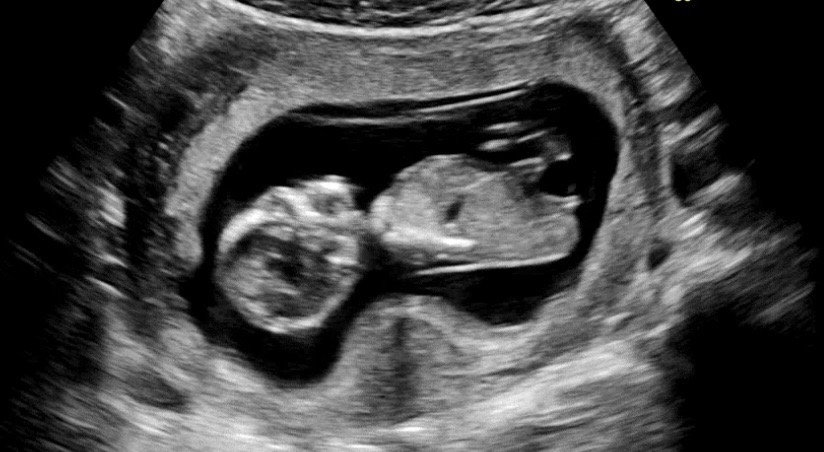

12주차3일 각도법

딸일까요 아들일까요??

딸 같아보여요!

아들 같기도 해요!